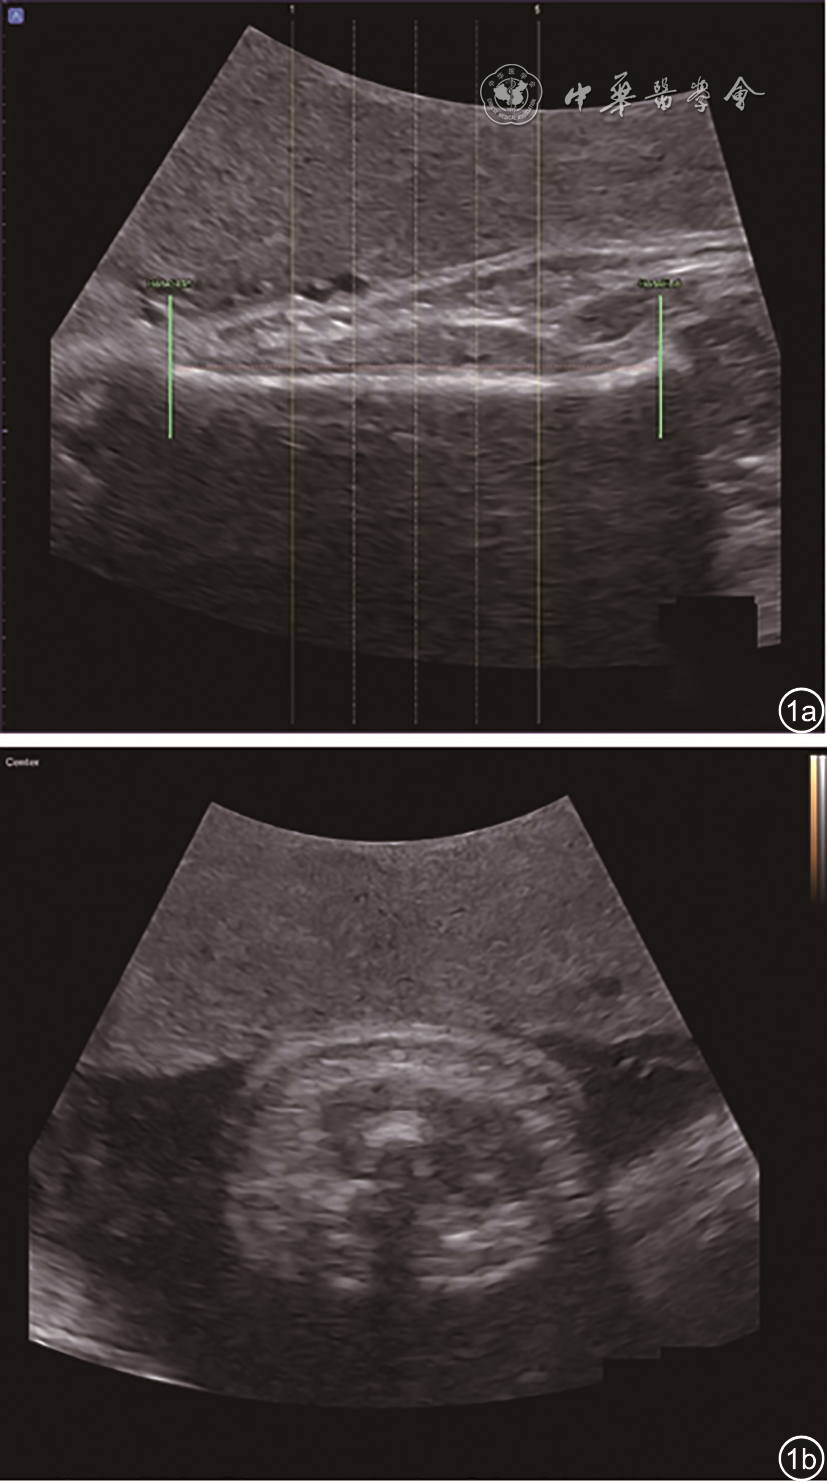

3. AVol的计算方法:通过新型软件(5D Limb Vol;Samsung Medison)计算半自动化的部分肢体容积测量值。该算法应用基于长轴长度、短轴长度和肢体中心坐标的图像变换方法。使用软件工具自动检测肱骨骨干的两端13。自动截取以肱骨中心的50%肱骨长度作5个等距横截面(图1)。描记每个肢体横截面边界,计算50%肱骨长度的肢体容积为AVol(图23)。

图1 正常出生体质量儿上臂三维容积超声扫描图。图a为肱骨长轴切面,以肱骨中心的50%肱骨长度作5个等距横截面;图b为肱骨中心所在的上臂横截面